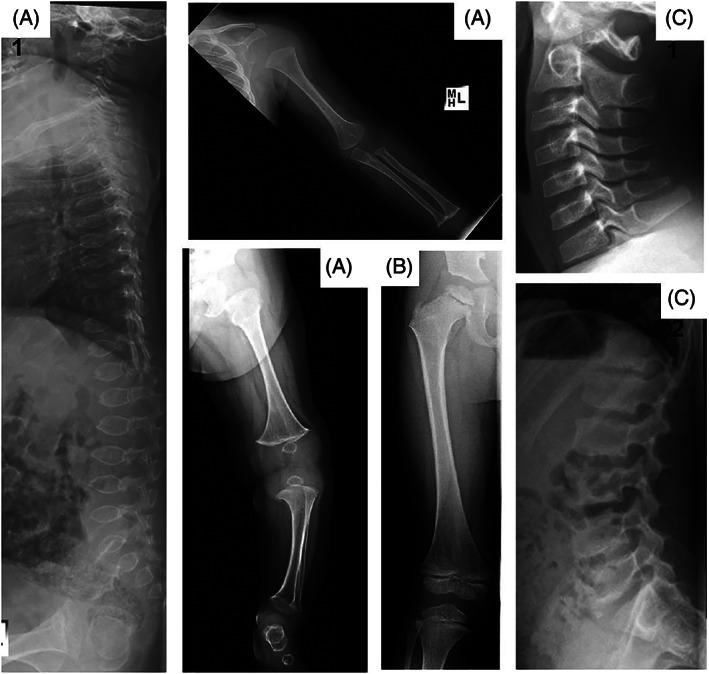

Sulfate is the fourth most abundant anion in human plasma but is not measured in clinical practice and little is known about the consequences of sulfate deficiency. Nevertheless, sulfation plays an essential role in the modulation of numerous compounds, including proteoglycans and steroids. We report the first patient with a homozygous loss-of-function variant in the SLC13A1 gene, encoding a renal and intestinal sulfate transporter, which is essential for maintaining plasma sulfate levels. The homozygous (Arg12Ter) variant in SLC13A1 was found by exome sequencing performed in a patient with unexplained skeletal dysplasia. The main clinical features were enlargement of joints and spondylo-epi-metaphyseal radiological abnormalities in early childhood, which improved with age. In addition, autistic features were noted. We found profound hyposulfatemia due to complete loss of renal sulfate reabsorption. Cholesterol sulfate was reduced. Intravenous N-acetylcysteine administration temporarily restored plasma sulfate levels. We conclude that loss of the SLC13A1 gene leads to profound hypersulfaturia and hyposulfatemia, which is mainly associated with abnormal skeletal development, possibly predisposing to degenerative bone and joint disease. The diagnosis might be easily missed and more frequent.

硫酸盐是人体血浆中第四丰富的阴离子,但在临床实践中并未测量,并且对硫酸盐缺乏的后果知之甚少。尽管如此,硫酸化在调节许多化合物(包括蛋白聚糖和类固醇)方面起着至关重要的作用。我们报告了首例 SLC13A1 基因纯合功能丧失变异的患者,该基因编码一种肾脏和肠道硫酸盐转运蛋白,对于维持血浆硫酸盐水平至关重要。在一名患有不明原因骨骼发育不良的患者中,通过外显子组测序发现 SLC13A1 的纯合(Arg12Ter)变异。主要的临床特征是在幼儿时期关节肿大和脊椎-骺-干骺端放射学异常,随着年龄的增长而改善。此外,还注意到自闭症特征。我们发现由于肾脏硫酸盐重吸收完全丧失而导致严重的低硫酸盐血症。胆固醇硫酸盐减少。静脉注射 N-乙酰半胱氨酸可暂时恢复血浆硫酸盐水平。我们得出结论,SLC13A1 基因的缺失导致严重的高硫酸盐血症和低硫酸盐血症,主要与异常的骨骼发育有关,可能易患退行性骨和关节疾病。该诊断可能容易被忽视,并且更为常见。